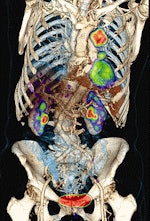

![]() |

| Above, PET and PET/CT fused data post-therapy for lymphoma. Below, PET and PET/CT fused data pretherapy for lymphoma. The images illustrate a patient's lymphoma staging to assess initial treatment strategy and follow-up study after initial treatment to plan subsequent treatment. The images were taken by Philips Healthcare's Gemini TF with time-of-flight. Images courtesy of Philips and University Hospitals Case Medical Center in Cleveland. |